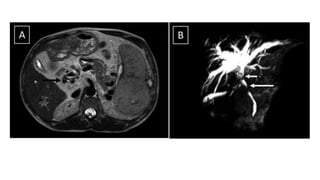

• Magnetic Resonance Cholangiopancreaticography

• It is the imaging of choice to evaluate biliary changes.

• The findings include extrinsic indentation resulting in a wavy contour

of the biliary duct, focal stricture with upstream dilatation, and sharp

angulation of the bile duct.

• Magnetic ResonanceCholangiopancreaticography • It is the imaging of choice to evaluate biliary changes. • The findings include extrinsic indentation resulting in a wavy contour of the biliary duct, focal stricture with upstream dilatation, and sharp angulation of the bile duct.

• #29 T2-weighted axial section shows multiple tortuous vascular flow voids at the porta surrounding the biliary duct causing narrowing of lumen (black arrow). (B) Mrcp image shows short segments of narrowing in the extrahepatic bile duct and resultant bilobar symmetric intrahepatic bile duct